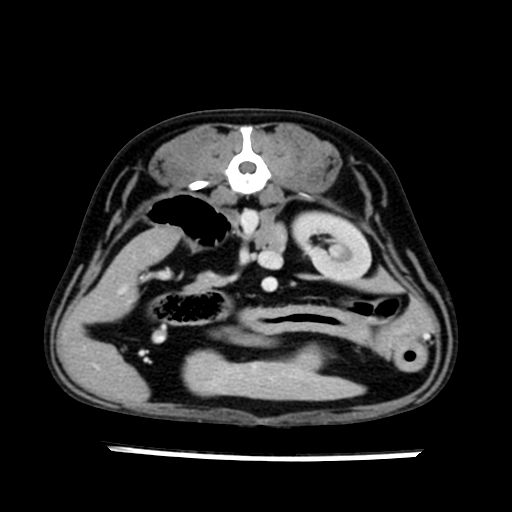

prescritto esame TAC

sequenza immagini limitata al fegato reni e surreni

le immagini ecografiche rispetto alla tac datano circa 7 mesi prima ,le surrenali sono normali nonostante il test acth sia risultato positivo .all’esame TAC dopo diversi mesi risultano aumentate armonicamente nel volume e si individua un forte sospetto di adenoma ipofisario .

sospetto adenoma ipofisario vs. meno probabilmente meningioma della base; intertiziopatia polmonare; lesione espansiva epatica, verosimilmente del lobo laterale sinistro, di sospetta natura neoplastica; lesioni spleniche di natura da definire; iperplasia/ipertrofia delle ghiandole surrenali, bilateralmente; vertebra di transizione del rachide toracico; tenosinovite cronica del muscolo bicipite brachiale di destra.

la tac dopo 7 mesi permette misure tridimensionali 5,2 x 9,2 x 4,5 cm (forma piu’ allungata )